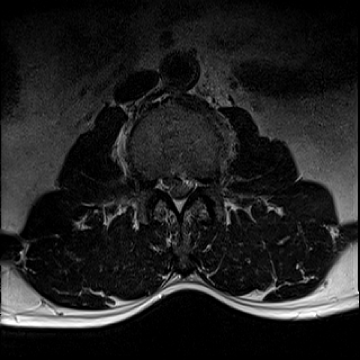

허리 디스크 수술 전·후

2022.08.01

2022.08.04

ㆍ환자 동의를 받은 자료이며, 이미지 사진은 실물과 다를 수 있습니다.

ㆍ모든 자료는 새움병원 자료입니다.